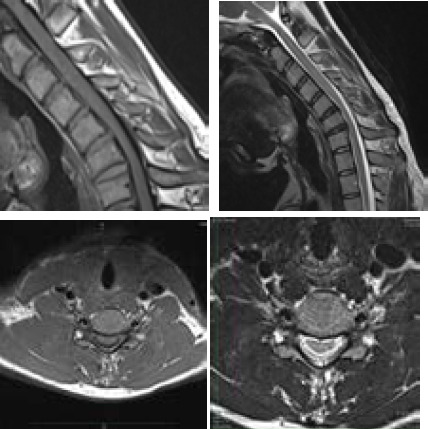

平山病是一种罕见的良性神经系统疾病,主要累及C5至T1脊髓前角,主要累及C7和C8。平山病是由于脊髓过度拉伸导致脊柱与硬脑膜之间生长不平衡,导致脊髓前部微循环紊乱,尤其是颈部屈曲时,引起单侧或很少不对称的双侧上肢无力和肌肉萎缩。这是一个21岁的男孩,他的左手和前臂虚弱了2年,在寒冷的天气和颈部弯曲时加重。颈部x线平片和颈椎MRI显示平山病的特征。

Hirayama disease is a rare benign neurological disease that affects the anterior horn of the spinal cord at C5 to T1, mainly at C7 and C8 due to imbalance growth between the vertebral column and the dura mater leading to microcirculatory disturbances in the anterior portion of the spinal cord due to overstretched cord, especially during flexion of the neck causing unilateral or rarely asymmetrically bilateral upper limb weakness and muscle wasting. It is a case of a 21-year-old boy presented with weaknesses in his left hand and forearm for 2 years which aggravates during cold weather and flexion of the neck. A plain x-ray of the neck and MRI of the cervical spine were conducted which show the features of Hirayama disease.